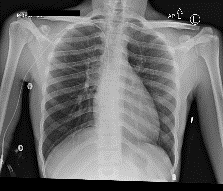

Among various medical imaging tools, chest radiographs are the most important and widely used diagnostic tool for detection of thoracic pathologies. Research is being carried out in order to propose robust automatic diagnostic tool for detection of pathologies from chest radiographs. Artificial Intelligence techniques especially deep learning methodologies have found to be giving promising results in automating the field of medicine. Lot of research has been done for automatic and fast detection of pneumothorax from chest radiographs while proposing several frameworks based on artificial intelligence and machine learning techniques. This study summarizes the existing literature for the automatic detection of pneumothorax from chest x-rays along with describing the available chest radiographs datasets. The comparative analysis of the literature is also provided in terms of goodness. Limitations of the existing literature along with the research gaps is also given for further investigation. The paper provides a brief overview of the present work for pneumothorax detection for helping the researchers in selection of optimal approach for future research.